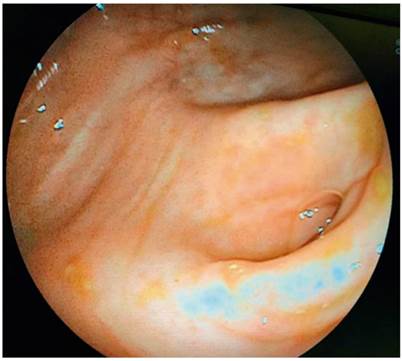

Mujer de 83 años sin antecedentes patológicos de interés, a quien se le realizó una colonoscopia diagnóstica y se encontraron múltiples divertículos en el colon sigmoide. La exploración completa tuvo una duración aproximada de 12 min y no se hallaron alteraciones en el ciego, así como tampoco en el orificio apendicular. Además, no se observaron otras alteraciones en el resto del colon (Figura 1). Por tanto, se le dio egreso a la paciente, sin que se evidenciara algún tipo de complicación inmediata.